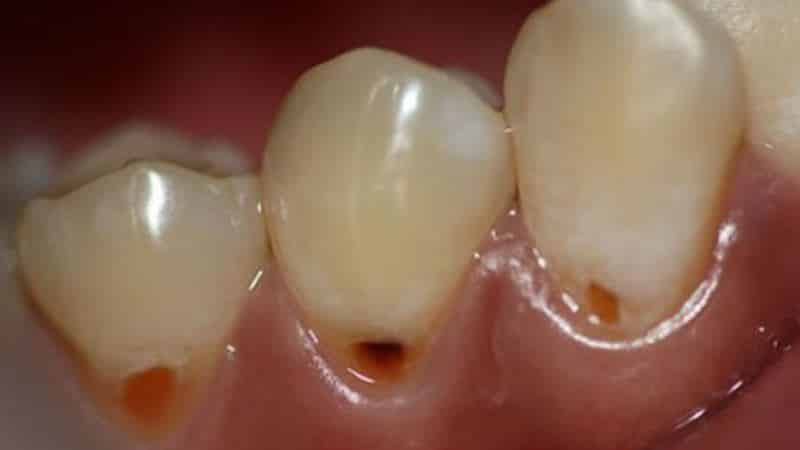

Из всех видов кариеса прикорневой считается наиболее опасным, так как он разрушает зубы, их корни и каналы. Это явление особенно часто наблюдается у пожилых пациентов и может привести к потере зубов. У таких больных часто возникают вопросы о том, что такое пришеечный кариес, как его лечить, какие причины его возникновения и как он выглядит на фотографиях. Давайте рассмотрим эти аспекты более подробно.

Данное заболевание проходит через несколько стадий, каждая из которых имеет свои признаки и методы лечения. Стадии развития кариеса могут быть следующими:

- Вторая стадия — на этом этапе развивается поверхностный кариес, который приводит к разрушению эмали. Появляется темное пятно, а также боль при употреблении сладкого, горячего, кислого, соленого и холодного. Лечение включает в себя препарирование и пломбировку пораженной области.